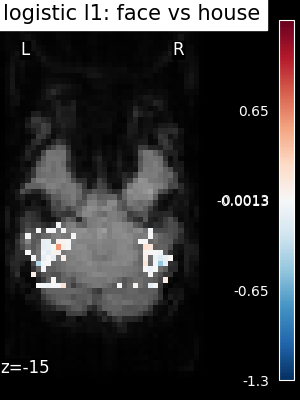

The corresponding weight maps (below) differ widely from one estimator to the other, although the prediction scores are fairly similar. In other terms, a well-performing estimator in terms of prediction error gives us little guarantee on the brain maps.

../_images/sphx_glr_plot_haxby_different_estimators_006.png ../_images/sphx_glr_plot_haxby_different_estimators_005.png ../_images/sphx_glr_plot_haxby_different_estimators_004.png ../_images/sphx_glr_plot_haxby_different_estimators_002.png ../_images/sphx_glr_plot_haxby_different_estimators_003.png